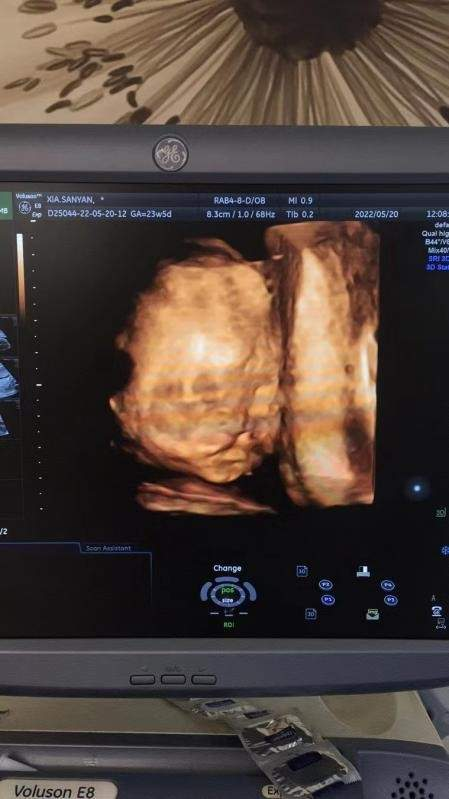

胎兒四維彩超影像

5月20日上午,懷孕23周的張女士來(lái)到武漢仁愛(ài)醫(yī)院準(zhǔn)備做四維彩超篩查。意外不期而至,武漢仁愛(ài)醫(yī)院超聲影像科主任王娟在檢查時(shí)對(duì)胎兒每個(gè)部位都進(jìn)行了仔細(xì)檢查,發(fā)現(xiàn)張女士腹中的寶寶患有先天性唇腭裂。

胎兒面部唇腭裂